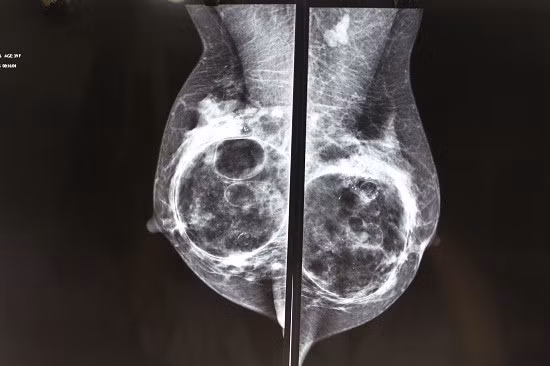

| Tuyến vú bị biến dạng với các cục, khối do nâng ngực bằng chất làm đầy. Ảnh: Bác sĩ cung cấp |

Bên cạnh đó, bệnh nhân cũng rất hay gặp trường hợp bị lộ túi hoặc có những bất thường vị trí, ngực sau khi làm không cân, túi chạy xê dịch theo vận động của cơ thể do dùng túi trơn,… Nhiều trường hợp còn bị bao xơ xung quanh, gây bóp chẹt, đau đớn, biến dạng ngực. Với biến chứng nhẹ hơn, bệnh nhân sẽ bị sẹo lồi ở đường mổ hoặc mất cảm giác của quầng vú do mổ không đúng cách.

Với các vật dụng nâng ngực bằng chất rắn đã ghép vào silicon dẻo, túi gel, việc lấy ra đơn giản hơn. Nhưng với những chất lỏng như silicon lỏng (đã bị cấm dùng) và những chất làm đầy phải thận trọng vì chỉ có thể lấy được một phần, phần còn lại ngấm vào các tổ chức và thường phải chờ chúng tự tiêu, mất ít nhất từ sáu tháng đến hai năm.